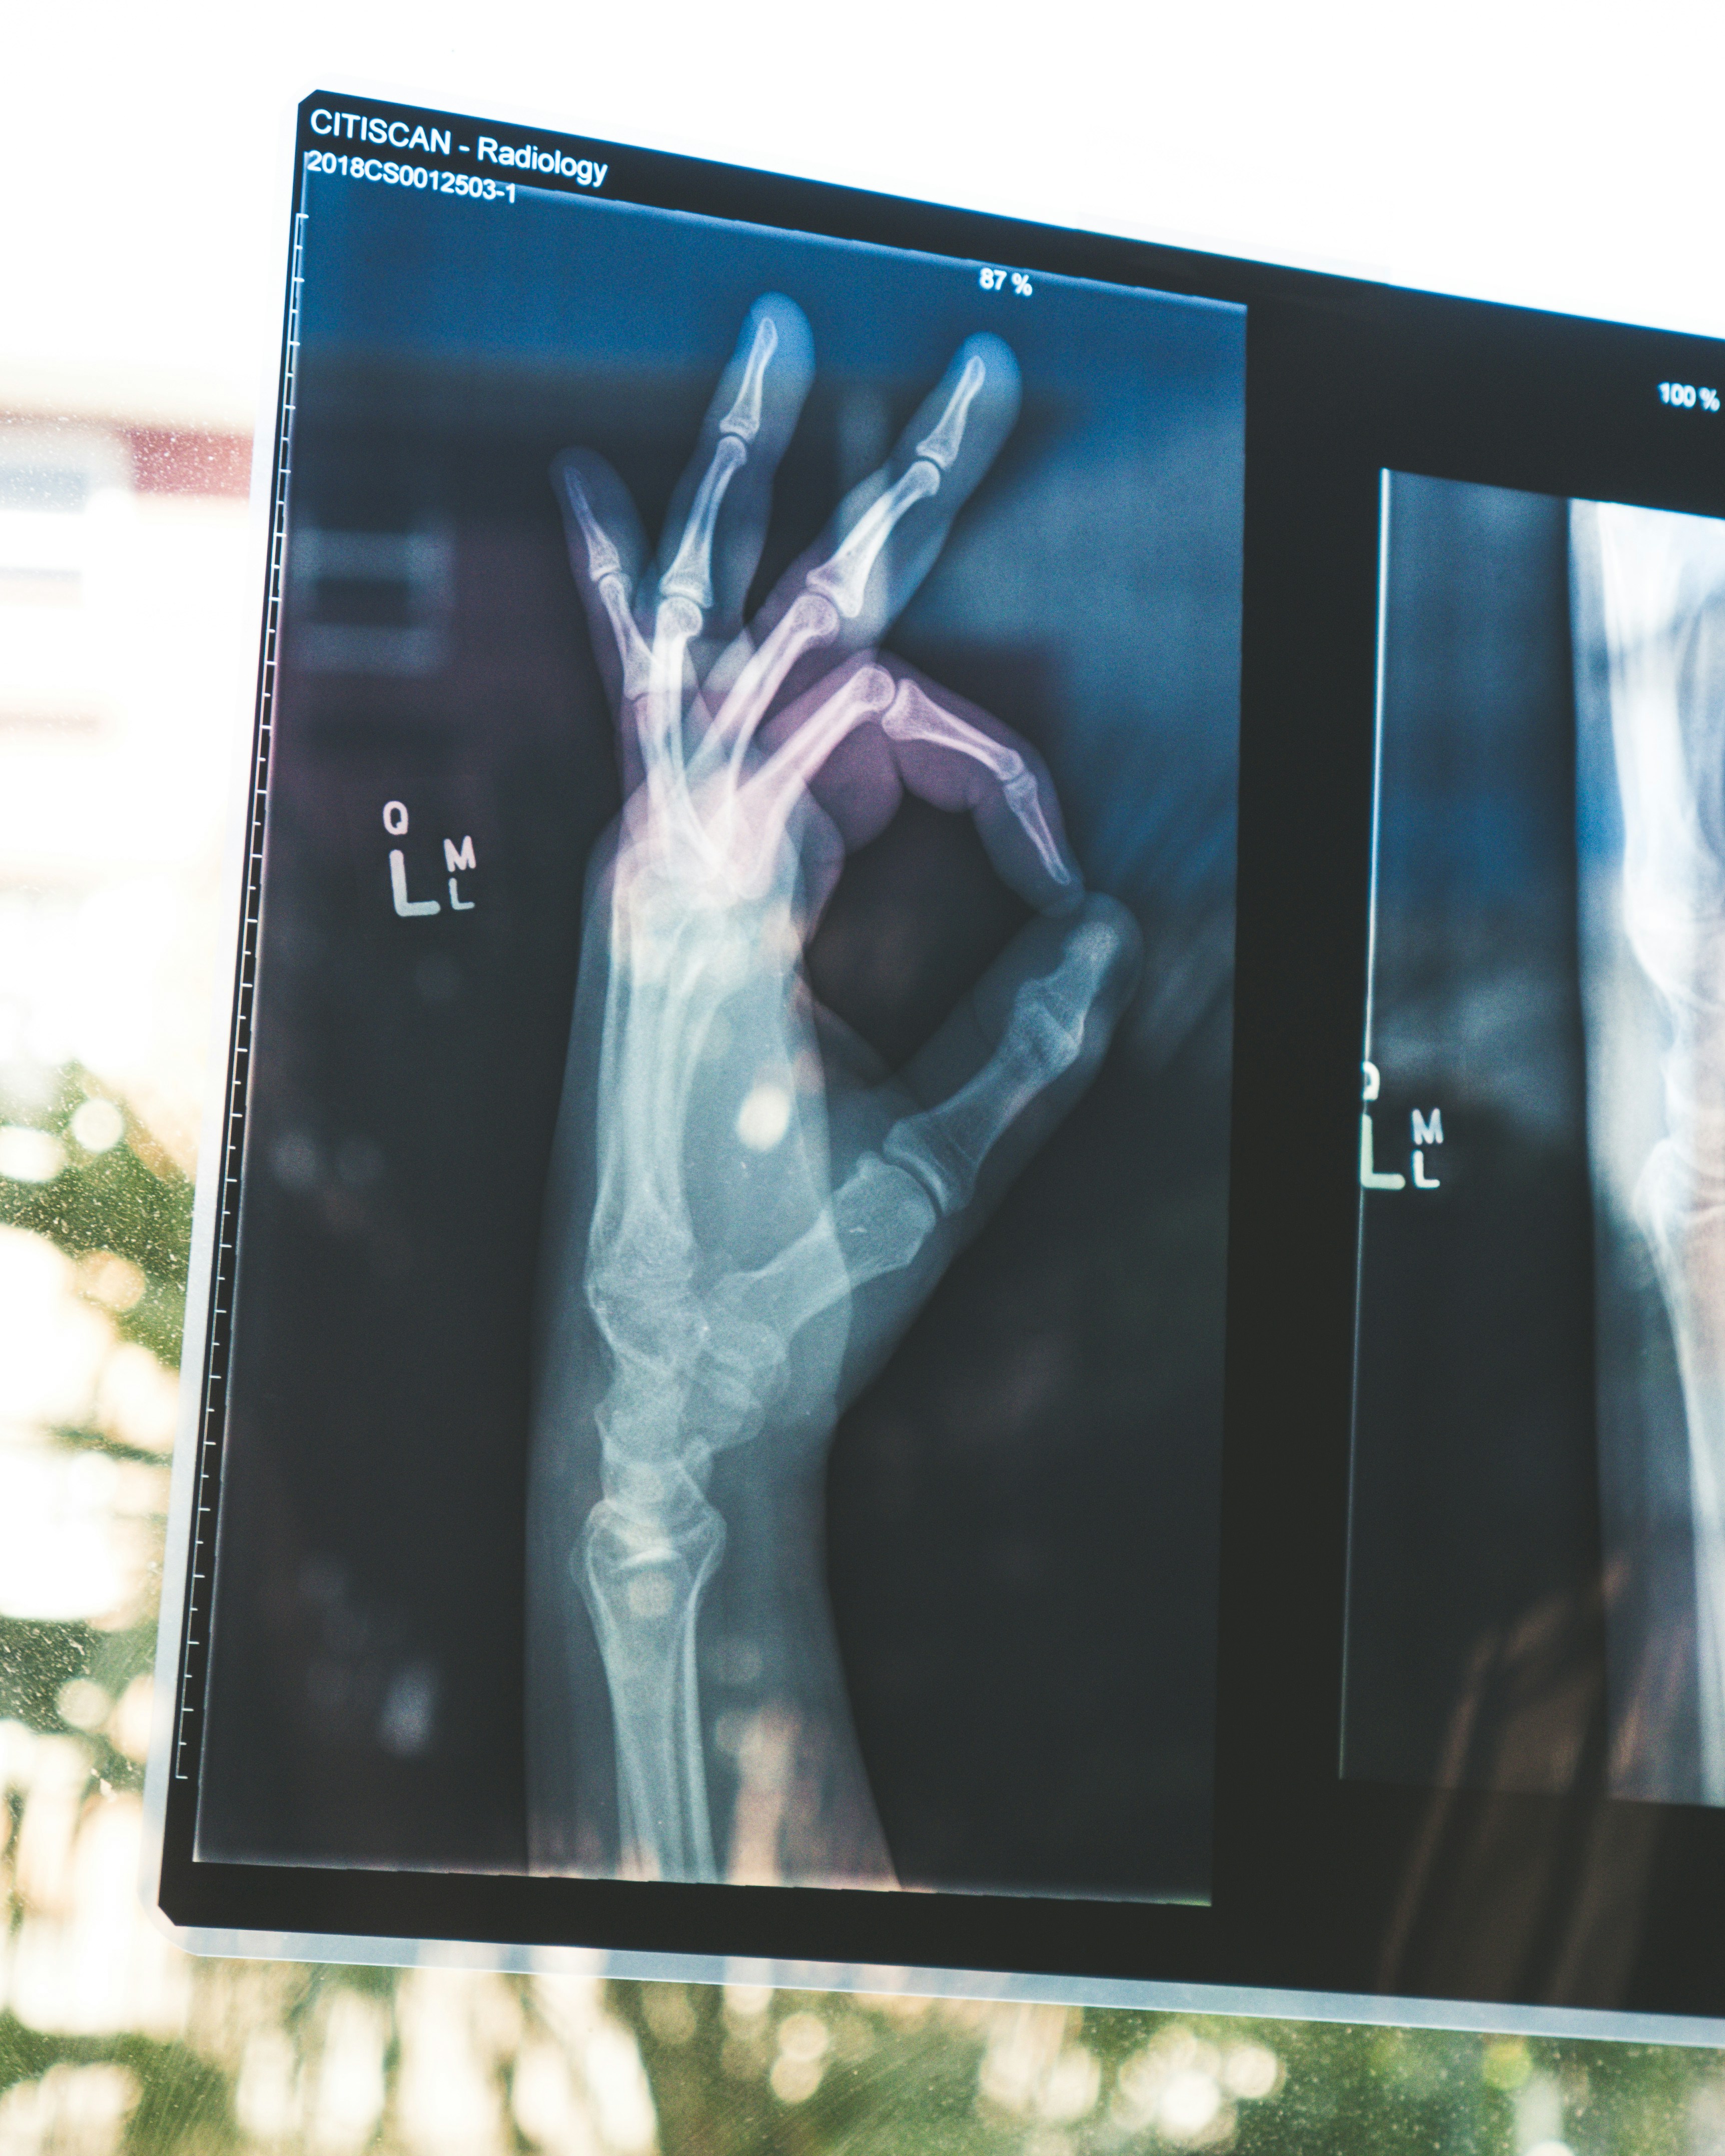

낙상은 단순 타박상이 아닌, 고관절·척추·손목 등 주요 뼈의 골절로 이어지며, 경우에 따라 수술과 입원 치료, 더 나아가 장기적인 신체 기능 저하로도 연결됩니다. 실제로 65세 이상 낙상 환자의 약 30%는 1년 내 재낙상을 경험하며, 회복 속도도 매우 느립니다.

고관절 골절(엉덩이 관절 부위)은 겨울철 낙상 부상 중 치명률과 후유증이 가장 높은 손상입니다. 걷거나 서는 데 필수적인 고관절은 골절 시 거의 대부분 수술이 필요하며, 수술 후에도 합병증이나 장기 입원 위험이 큽니다.

고관절 골절 환자의 경우 수술 후 6개월 내 사망률이 10~20%에 달한다는 연구도 있습니다. 이는 단순한 뼈 부상이 아닌, 신체 기능 전체를 저하시키는 큰 사고로 간주해야 합니다.